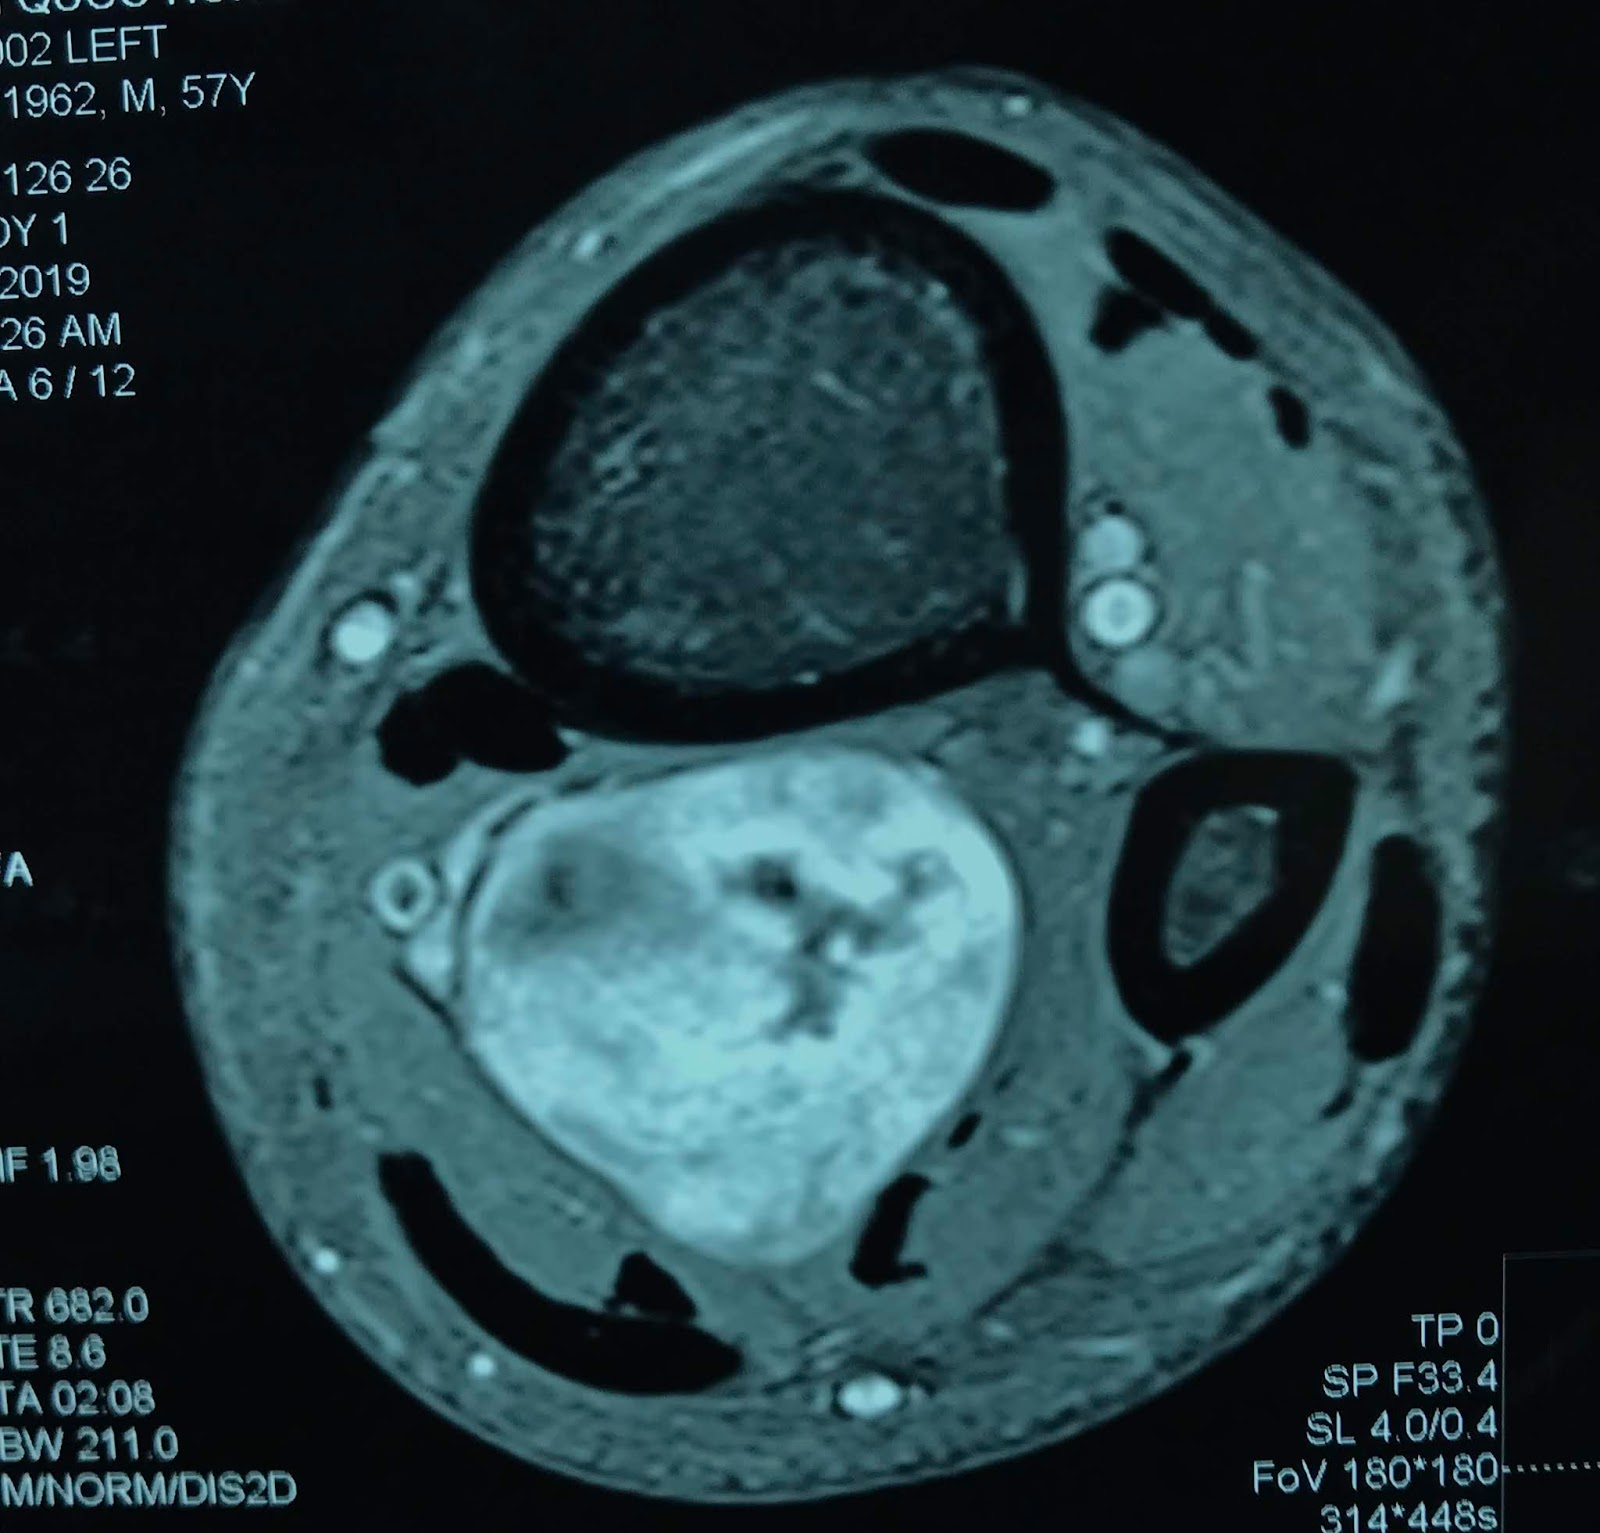

VIETNAMESE MEDIC ULTRASOUND CASE 440 MULTIPLE TUMORS of the LEG, Dr House Leg Tumor — house's leg injury was caused by an infarction while golfing, leading to severe pain and a dependency on vicodin. Towards the end of season 7 house took an. Soft tissue sarcomas are rare. Soft tissue sarcoma in lower leg muscle. What is soft tissue sarcoma? The injury and subsequent loss of personal agency shaped house's character, contributing to. House Leg Tumor.

VIETNAMESE MEDIC ULTRASOUND CASE 535 LOWER LEG TUMOR, Dr PHAN THANH House Leg Tumor why does house still have a limp after season 8? Soft tissue sarcoma in lower leg muscle. Soft tissue sarcomas are rare. — house's leg injury was caused by an infarction while golfing, leading to severe pain and a dependency on vicodin. What is soft tissue sarcoma? — sts tumors can occur anywhere in the body, but. House Leg Tumor.

VIETNAMESE MEDIC ULTRASOUND CASE 557 LEG TUMOR, Dr PHAN THANH HAI House Leg Tumor The injury and subsequent loss of personal agency shaped house's character, contributing to his arrogance and insistence on his own methods. Soft tissue sarcoma in lower leg muscle. — sts tumors can occur anywhere in the body, but more than half develop in a person’s arm or leg. Soft tissue sarcomas are rare. What is soft tissue sarcoma? Gregory. House Leg Tumor.

VIETNAMESE MEDIC ULTRASOUND CASE 557 LEG TUMOR, Dr PHAN THANH HAI House Leg Tumor Soft tissue sarcomas are rare. Soft tissue sarcoma in lower leg muscle. What is soft tissue sarcoma? Gregory house, (almost universally referred to as house and rarely as greg) is the main character and protagonist of the house series. Towards the end of season 7 house took an. — house's leg injury was caused by an infarction while golfing,. House Leg Tumor.

VIETNAMESE MEDIC ULTRASOUND CASE 535 LOWER LEG TUMOR, Dr PHAN THANH House Leg Tumor why does house still have a limp after season 8? — house's leg injury was caused by an infarction while golfing, leading to severe pain and a dependency on vicodin. — sts tumors can occur anywhere in the body, but more than half develop in a person’s arm or leg. Gregory house, (almost universally referred to as. House Leg Tumor.

VIETNAMESE MEDIC ULTRASOUND CASE 535 LOWER LEG TUMOR, Dr PHAN THANH House Leg Tumor What is soft tissue sarcoma? Towards the end of season 7 house took an. why does house still have a limp after season 8? Soft tissue sarcoma in lower leg muscle. Soft tissue sarcomas are rare. The injury and subsequent loss of personal agency shaped house's character, contributing to his arrogance and insistence on his own methods. Gregory house,. House Leg Tumor.